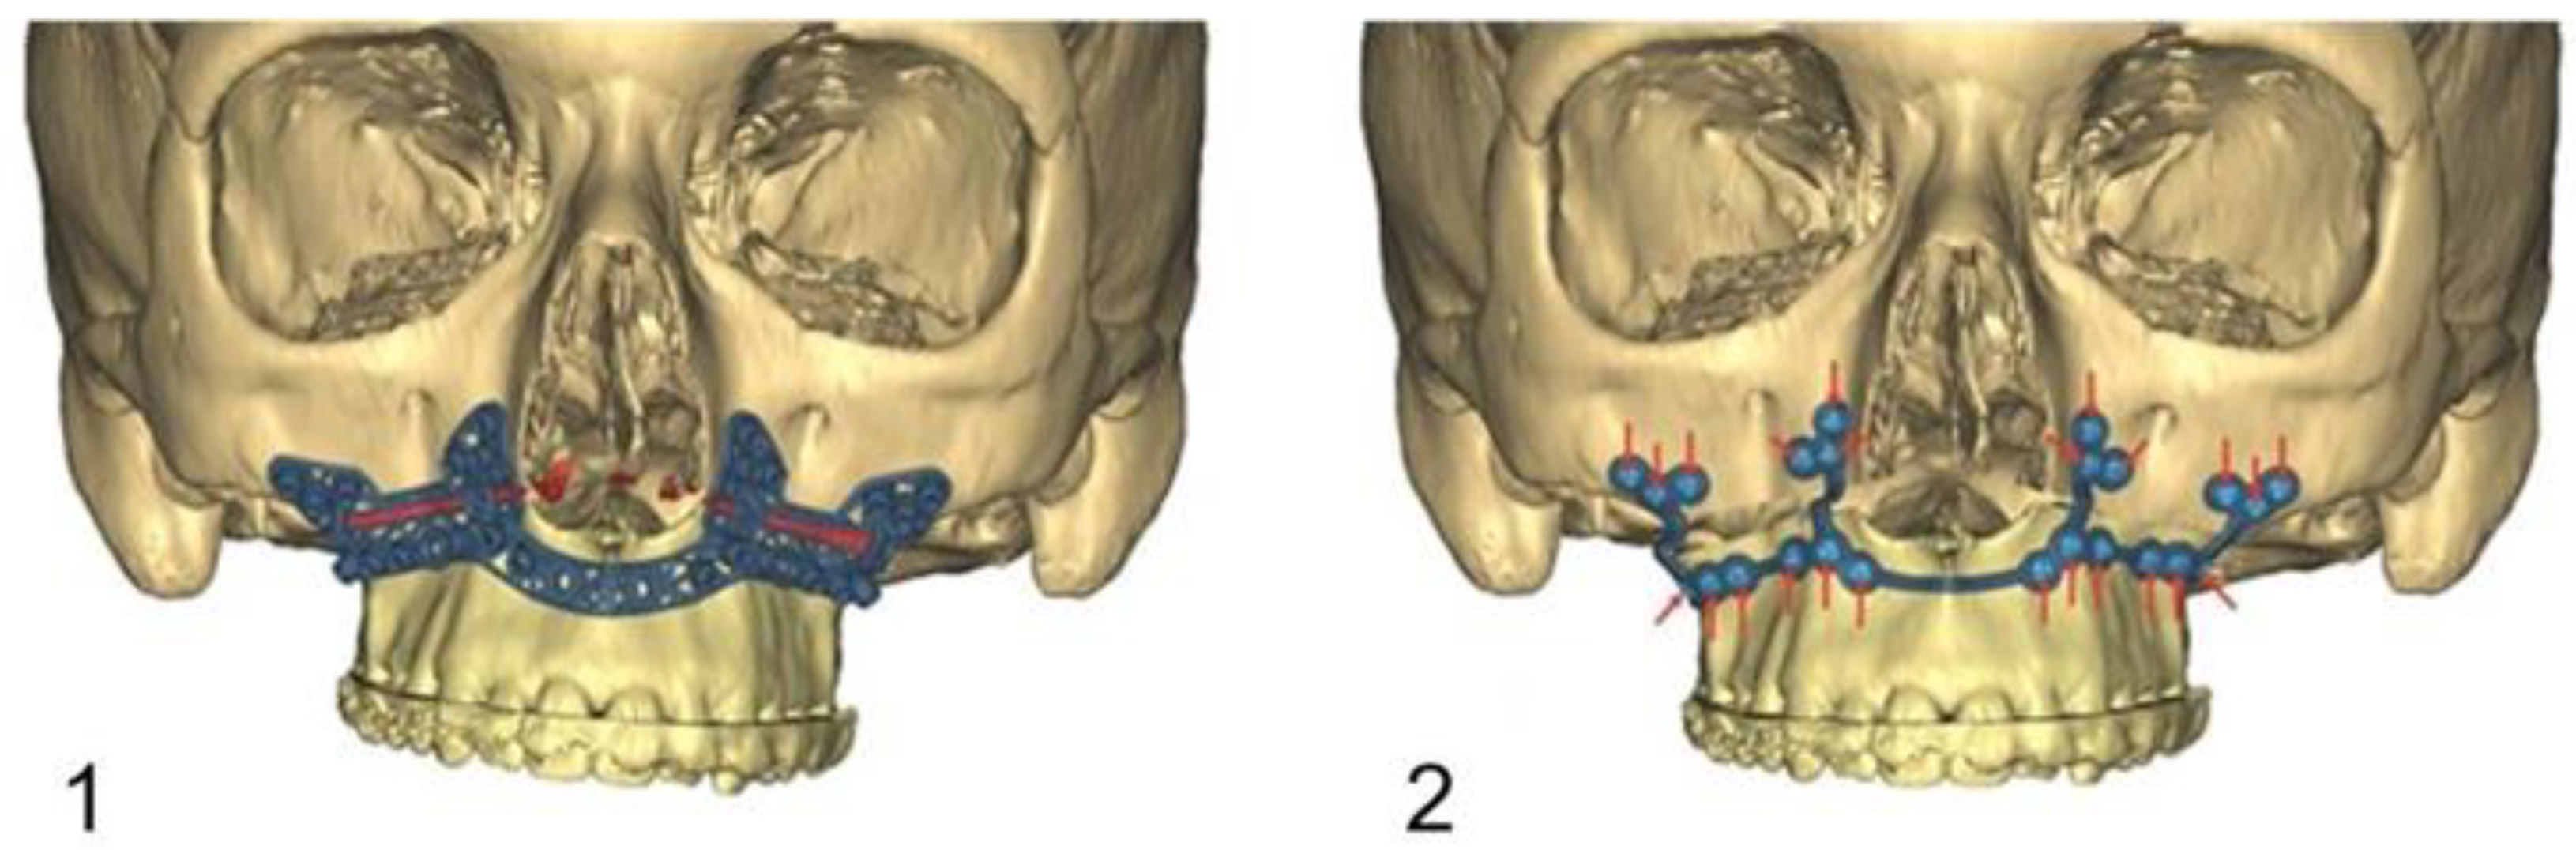

Figure 4.

Image (1): PSI fixed with osteosynthesis screws caudally to the maxillary osteotomy line. Image (2): Definitive fixation of the PSI after cranial mobilisation of the maxilla until it overlaps the predrilled holes.

The drilling/osteotomy template and the PSI was designed and manufactured by Materialise© (Leuven, Belgium) after an online planning session with the responsible surgeon team. In the planning, the pre-drilled holes and the osteosynthesis screws were positioned in such a way that the tooth roots were spared (Figure 2). The drilling/osteotomy template is passively and temporarily fixed to the maxillary bone with two to a maximum of four additional osteosynthesis screws. The holes for the subsequent osteosynthesis are then drilled both cranially and caudally to the osteotomy using the drill/osteotomy templates preformed drill channels. The Le Fort I osteotomy line is guided in the area of the anterior and lateral walls of the maxillary sinus as virtually planned and is completed after removal of the drill/osteotomy template. After “down fracture”, the patient-specific implant is passively placed on the caudal mobile maxilla and fixed with screws through the already predrilled holes. The design and shape of the patient-specific implant encodes the final position of the maxilla in all three planes with a secure and reproducible fit (Figure 3). Therefore, the maxillary positioning can be performed intraoperatively, independently of the mobile mandible. The maxilla is moved cranially until the empty screw holes of the PSI are also passively positioned over the pre-drilled holes in the cranial part on both sides of the midface. The PSI fixation follows by using monocortical osteosynthesis screws with a diameter of 1.85 mm and a typical length of 4 mm (Figure 4).